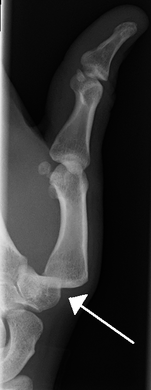

X-rays are usually taken to confirm a diagnosis and detect any fractures which may also have occurred at the time of dislocation. A dislocation is easily seen on an X-ray.[8]

- Finger: Interphalangeal (IP) or metacarpophalangeal (MCP) joint dislocations[15]

Radiograph of right fifth phalanx bone dislocation- Radiograph of left index finger dislocation

Radiograph of right fifth phalanx dislocation resulting from bicycle accident- Right fifth phalanx dislocation resulting from bicycle accident